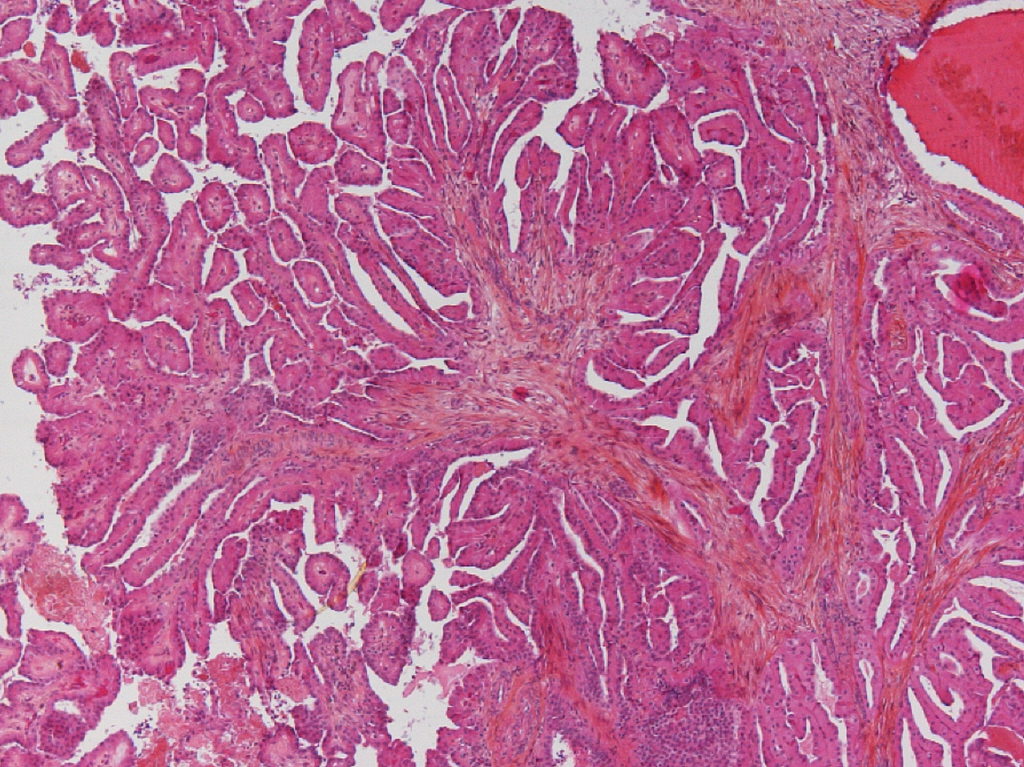

Classification of renal tumors